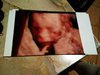

Moja dzisiaj ( 20.4 tydz) wyszło ze waży 375 g i się zastanawiam czy to mało czy dużo

Mój synek w 20+1 ważył 387gIle wasze dzidzie ważyły w 20/21 tygodniu?